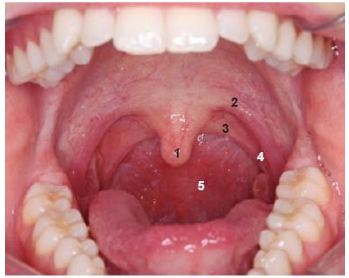

Levando em consideração a estrutura bucal, analise a imagem e estabeleça a relação com a denominação e número:

A sequência CORRETA é: